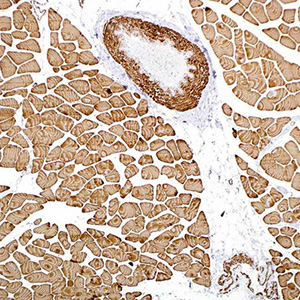

Актин является основным компонентом цитоскелета. Данное антитело выявляет актин в клетках скелетных, сердечных и гладких мышц. Оно не вступает в реакцию с другими мезенхимными клетками, кроме миоэпителия. Актин, исходя из его изоэлектрических характеристик, можно разделить на три различных компонента: альфа, бета и гамма, в порядке увеличения изоэлектрической точки. Антитело к специфическому для мышц актину распознает альфа и гамма изотипы всех групп мышц. Немышечные клетки, такие как сосудистые эндотелиальные клетки и клетки соединительной ткани, не окрашиваются этим антителом. Также отрицательными являются клетки опухолей немышечного происхождения, такие как карциномы, меланомы и лимфомы. Данное антитело очень полезно для идентификации рабдоидных клеточных элементов.